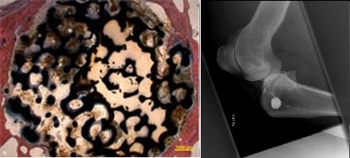

Der Schwerpunkt im Bereich "Medizintechnische Werkstoffe" liegt auf der Forschung und Entwicklung von Werkstoffen und Implantaten für die Orthopädie, die Kardiologie, die Mund-, Kiefer und Gesichtschirurgie sowie für Dentalimplantate. Der Fokus dabei liegt auf der Erforschung pulvermetallurgisch basierter Werkstoffe und Verfahren sowie des multimaterialbasierten Ansatzes von Funktionswerkstoffen. Das besondere Interesse gilt der Erforschung von Funktionswerkstoffen mit bioresorbierbaren Eigenschaften, zum Beispiel für Stents oder für den Ersatz knöcherner Strukturen. Darüber hinaus beschäftigt sich die Arbeitsgruppe mit der Entwicklung hochporöser zellularer metallischer Werkstoffe, die sich besonders gut für den Ersatz spongiösen Knochens eignen.